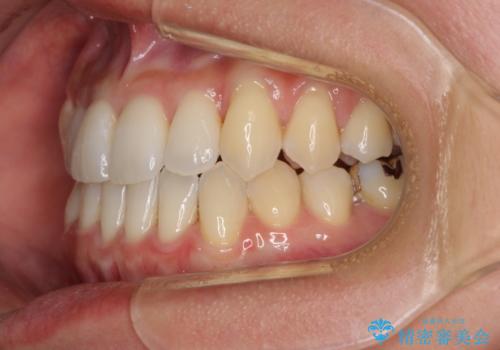

前歯のデコボコ インビザラインによる矯正治療

- 上下前歯の叢生と奥歯の反対咬合を気にして来院された患者様です。

インビザラインを用い、下顎はIPR(歯と歯の間を削る)と歯列全体を後方に移動させ、上顎は側方に拡大させることで歯列を改善していくこととしました。

骨格的に下顎が左側前方にずれているため、上下正中のズレや左右奥歯の咬み合わせを理想的な状態とすることは困難でした。